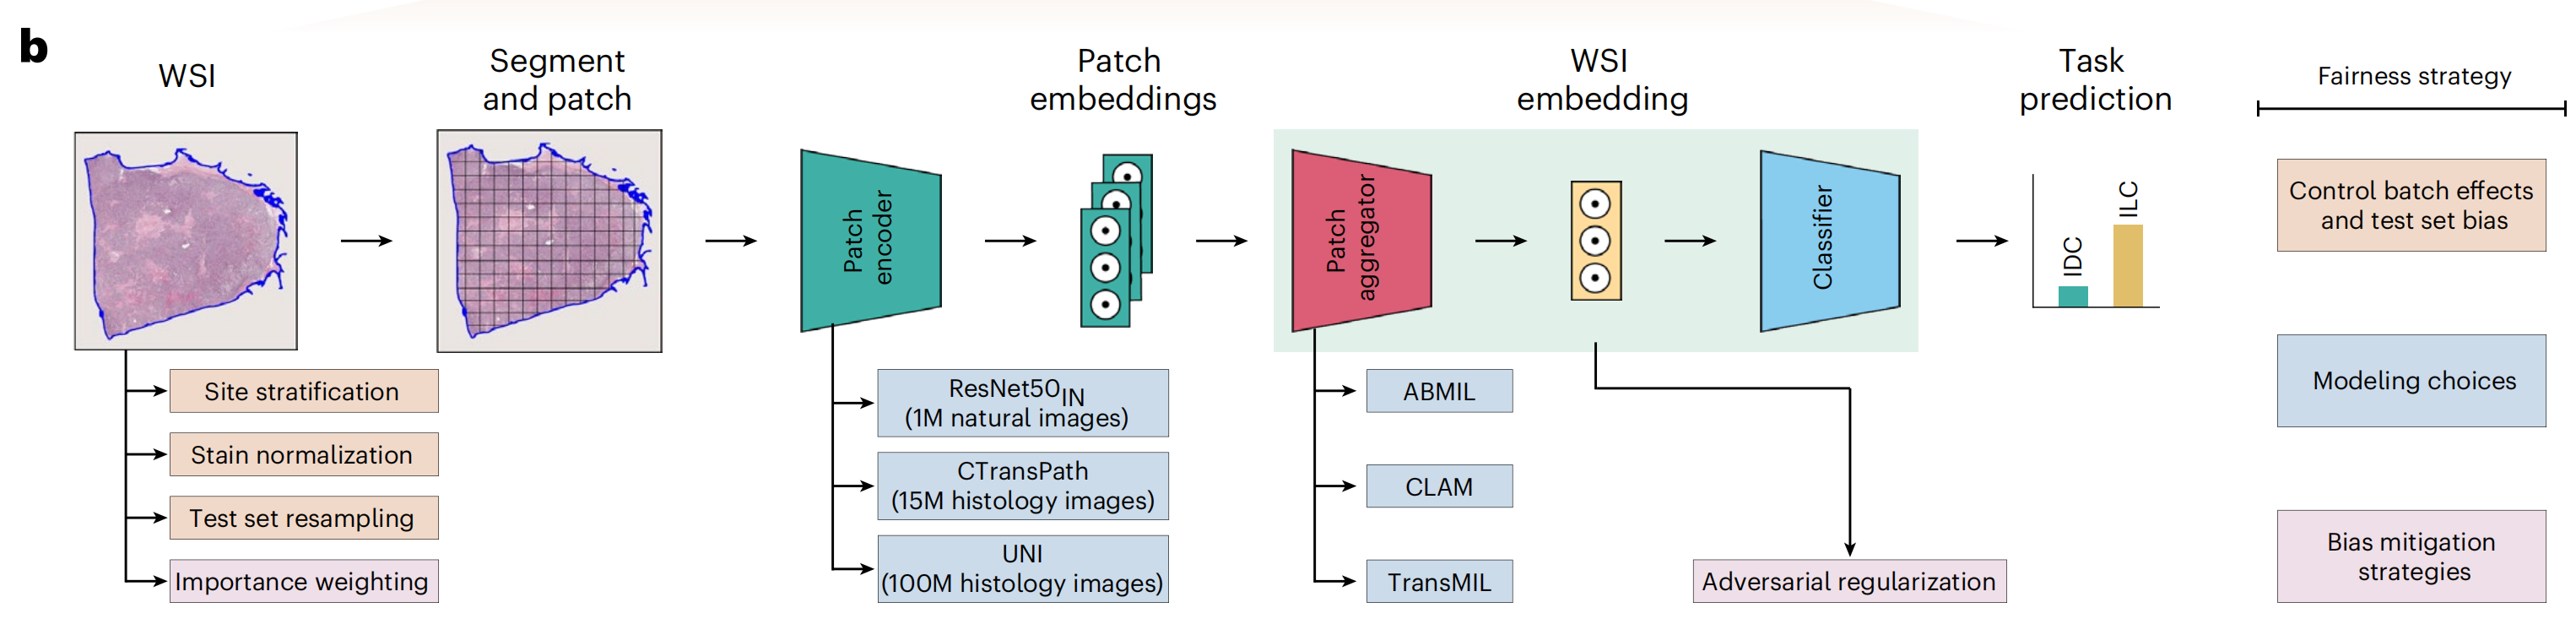

这篇文章发表在《Nature Medicine》2024年4月号上,题为《Demographic bias in misdiagnosis by computational pathology models》,作者包括Anurag Vaidya, Richard J. Chen, Drew F. K. Williamson等多位研究人员。文章主要探讨了在计算病理学模型中,人口统计因素对性能的影响,尤其是这些模型在对乳腺癌和肺癌亚型分类以及胶质瘤中IDH1突变预测时,对不同人群可能存在的偏见和误差。

文章指出,尽管计算病理学系统获得了越来越多的监管批准,但基于深度学习的系统经常忽视人口统计因素对性能的影响,可能导致偏见。这一问题尤为重要,因为计算病理学依赖于大型公共数据集,而这些数据集往往不能充分代表某些人群。研究使用了来自癌症基因组图谱(The Cancer Genome Atlas, TCGA)和EBRAINS脑肿瘤图谱的公开数据,以及内部患者数据,展示了在不同人群之间存在显著的性能差异。

研究结果表明,使用常见的建模方法时,白人和黑人患者在乳腺癌亚型分类、肺癌亚型分类以及胶质瘤中IDH1突变预测方面的性能差距分别为3.0%、10.9%和16.0%。研究发现,通过自监督视觉基础模型获得的丰富特征表示可以减少群体间性能差异。即便如此,自监督视觉基础模型并不能完全消除这些差异,这突显了在计算病理学中持续需要努力减轻偏见。

文章还讨论了数据特征、模型架构和偏见缓解策略对模型公平性和性能的影响,并建议监管和政策机构在评估指南中整合人口统计分层评估。此外,研究还发现,即使在考虑了与人群相关的数据特征后,不同种族群体之间的性能差异仍然存在,这表明需要在计算病理学中进一步研究和解决这些差异。

文章最后强调,为了提高计算病理学模型的公平性和性能,需要采取多种措施,包括使用自监督学习、改进数据预处理技术、实施偏见缓解策略,并确保在不同人群中进行充分的模型评估和测试。

Fig. 1 展示了在研究中使用的三个数据集(TCGA、MGB和EBRAINS脑肿瘤图谱)的特征、研究中使用的公平性指标以及建模选择。

以下是对图的详细分析:

a 部分展示了用于研究的三个数据集的组成,包括它们包含的用于诊断算法研究的幻灯片数量。这些数据集用于调查在最小化行动学习(MIL)幻灯片级别癌症诊断算法中的人口统计偏差,具体是针对乳腺癌和肺癌亚型分类以及胶质瘤中IDH1突变预测。研究使用了种族分层的ROC AUC(接收者操作特征曲线下面积)、TPR差异(真正例率差异)和独立测试队列上的种族预测来调查差异。

b 部分描述了MIL计算病理学研究中使用的深度学习(DL)管道的不同阶段,包括组织分割和贴片、使用贴片编码器映射到低维表示,以及分类。图中还展示了与公平性相关的技术,包括控制批次效应和测试集偏差、建模选择和偏见缓解策略。

c 和 d 部分介绍了研究中使用的两种常见的偏见缓解策略。c 部分描述了重要性加权(IW),这是一种通过与它们在总人口中的大小成反比地对种族群体中的患者进行采样,以确保公平代表性的方法。d 部分描述了对抗性正则化(AR),这是一种通过使嵌入对种族不可知来缓解偏见的策略。通过最大化辅助种族分类器的损失来实现这一点。

总体而言,Fig. 1 提供了对研究中使用的数据集、评估方法和偏见缓解策略的全面视图,并通过可视化手段展示了不同技术对减少种族间性能差异的潜在影响。